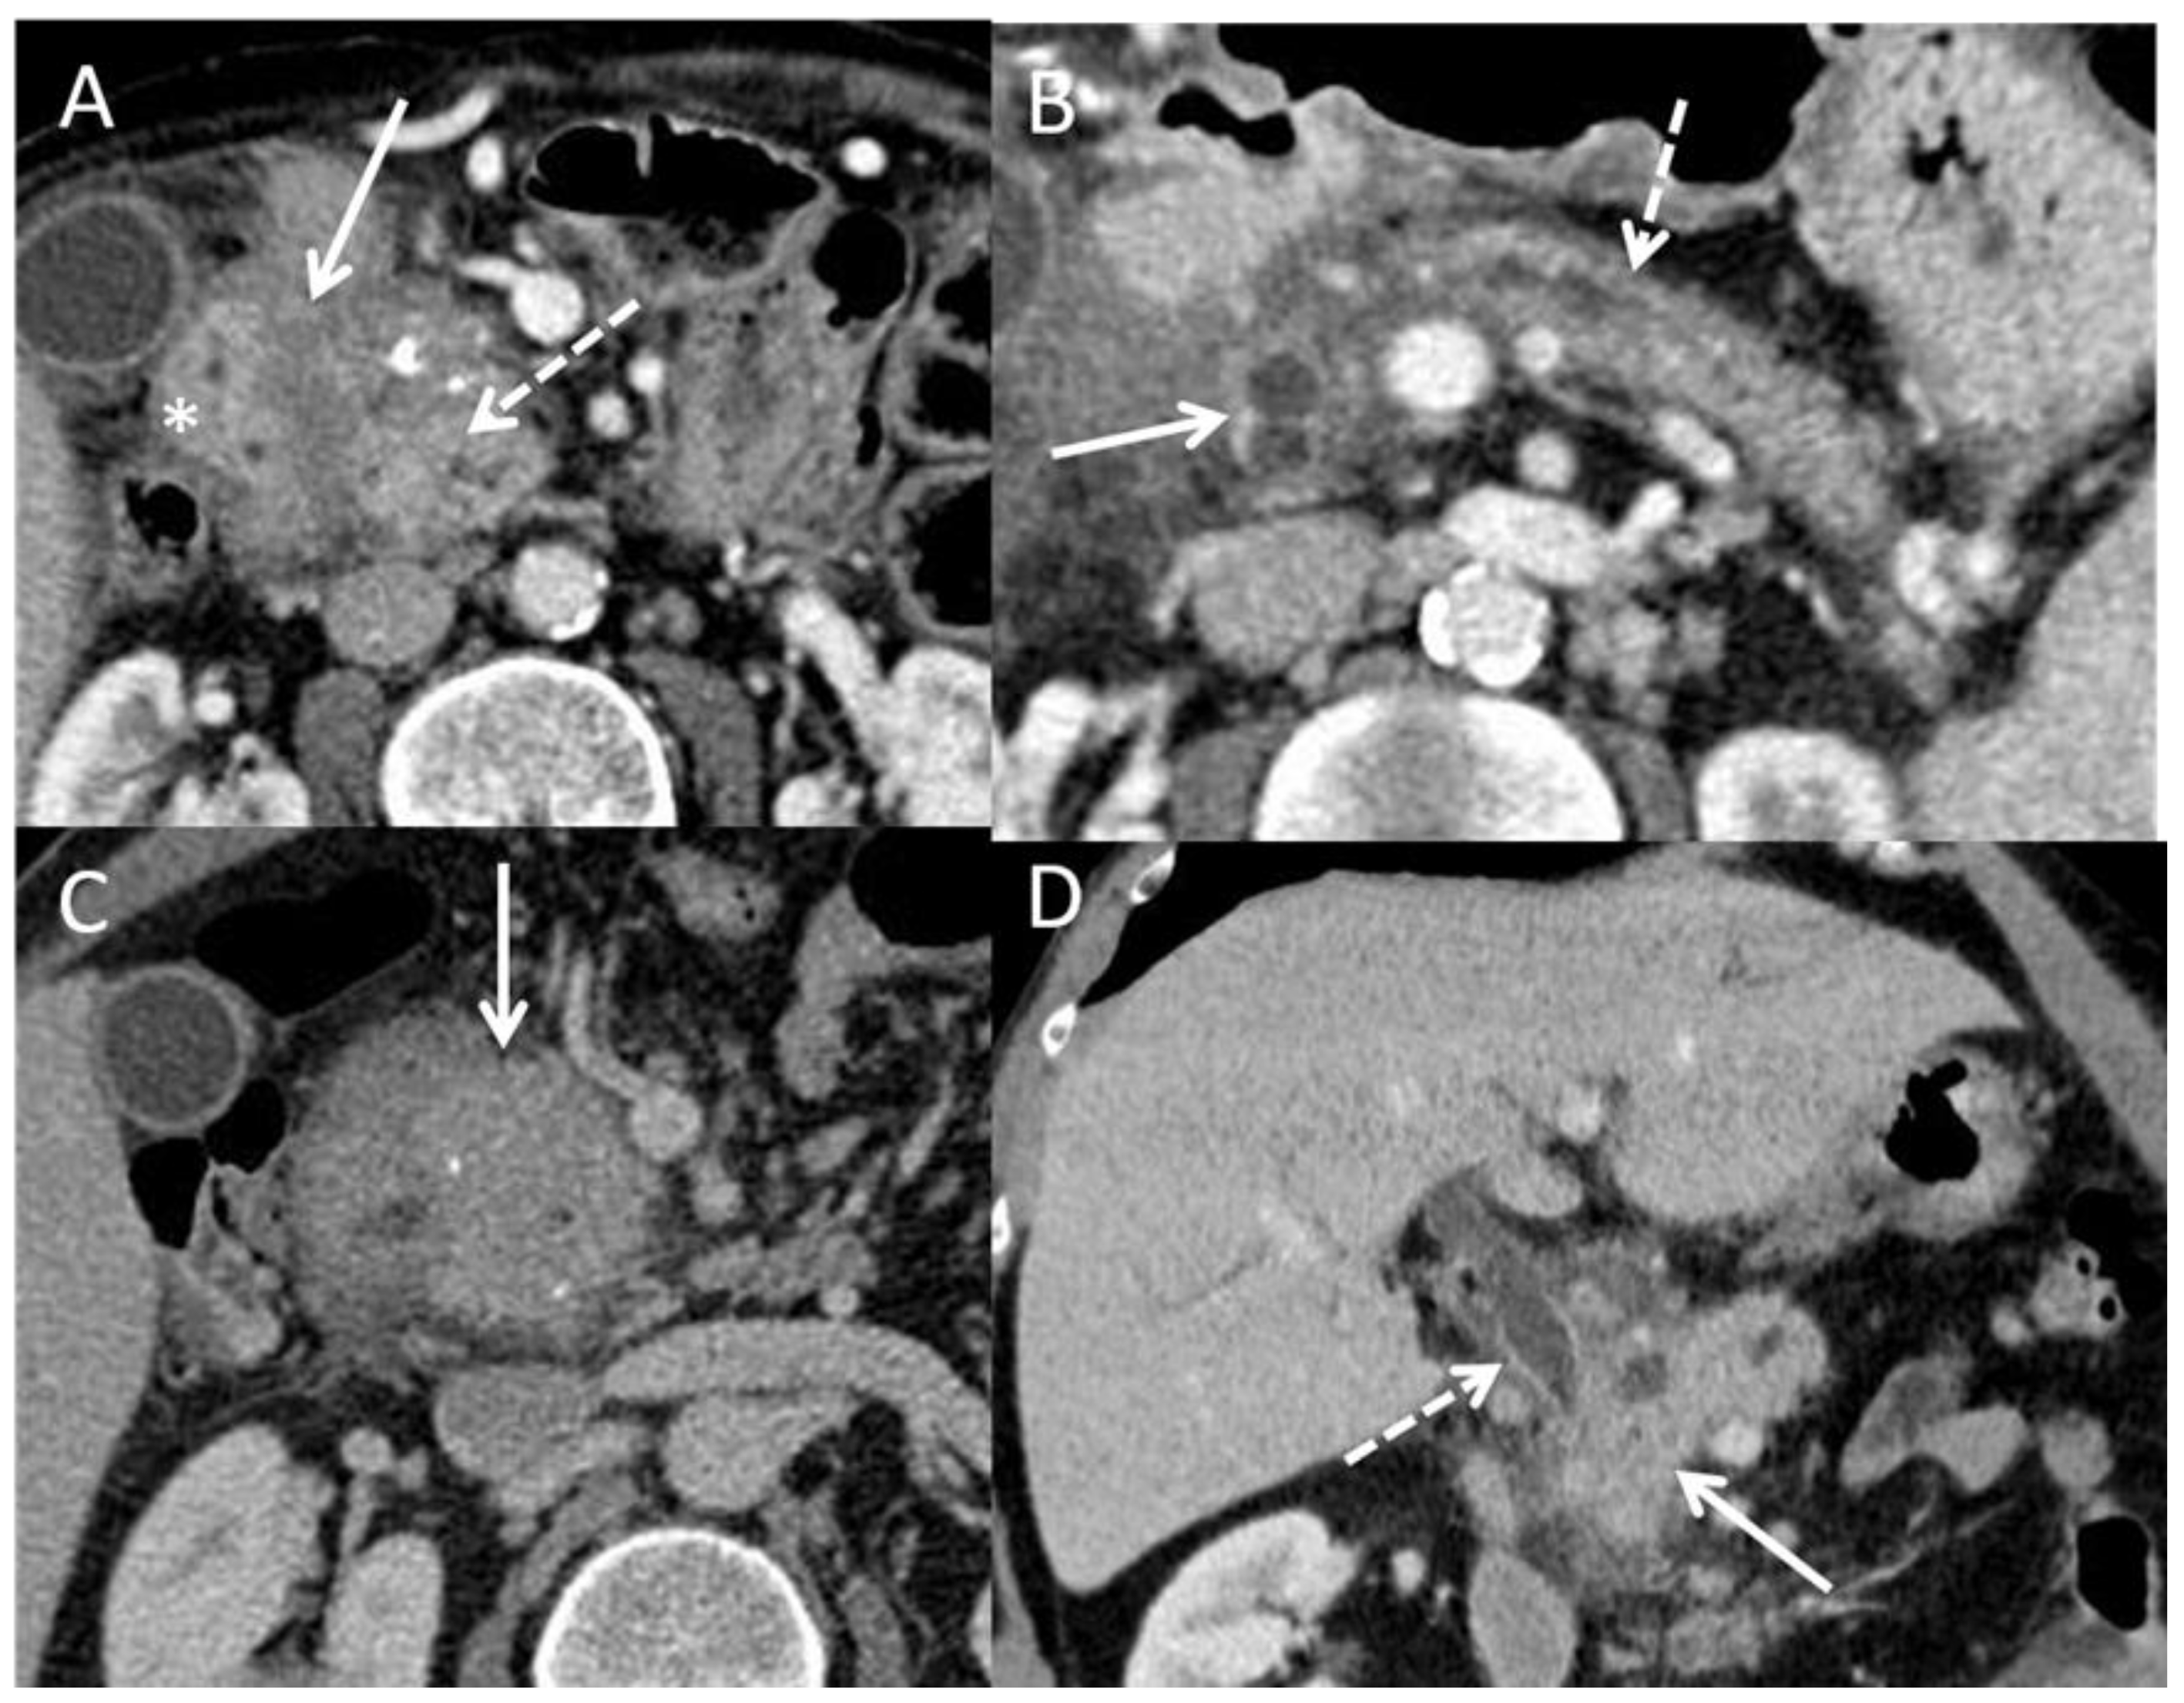

- Wolske, K.M.; Ponnatapura, J.; Kolokythas, O.; Burke, L.M.B.; Tappouni, R.; Lalwani, N. Chronic Pancreatitis or Pancreatic Tumor? A Problem-Solving Approach. RadioGraphics 2019, 39, 1965–1982. [Google Scholar] [CrossRef]

- Schima, W.; Böhm, G.; Rösch, C.S.; Klaus, A.; Függer, R.; Kopf, H. Mass-Forming Pancreatitis versus Pancreatic Ductal Adenocarcinoma: CT and MR Imaging for Differentiation. Cancer Imaging 2020, 20, 52. [Google Scholar] [CrossRef]

- Elsherif, S.B.; Virarkar, M.; Javadi, S.; Ibarra-Rovira, J.J.; Tamm, E.P.; Bhosale, P.R. Pancreatitis and PDAC: Association and Differentiation. Abdom. Radiol. 2020, 45, 1324–1337. [Google Scholar] [CrossRef]

- Srisajjakul, S.; Prapaisilp, P.; Bangchokdee, S. CT and MR Features That Can Help to Differentiate between Focal Chronic Pancreatitis and Pancreatic Cancer. Radiol. Med. 2020, 125, 356–364. [Google Scholar] [CrossRef]